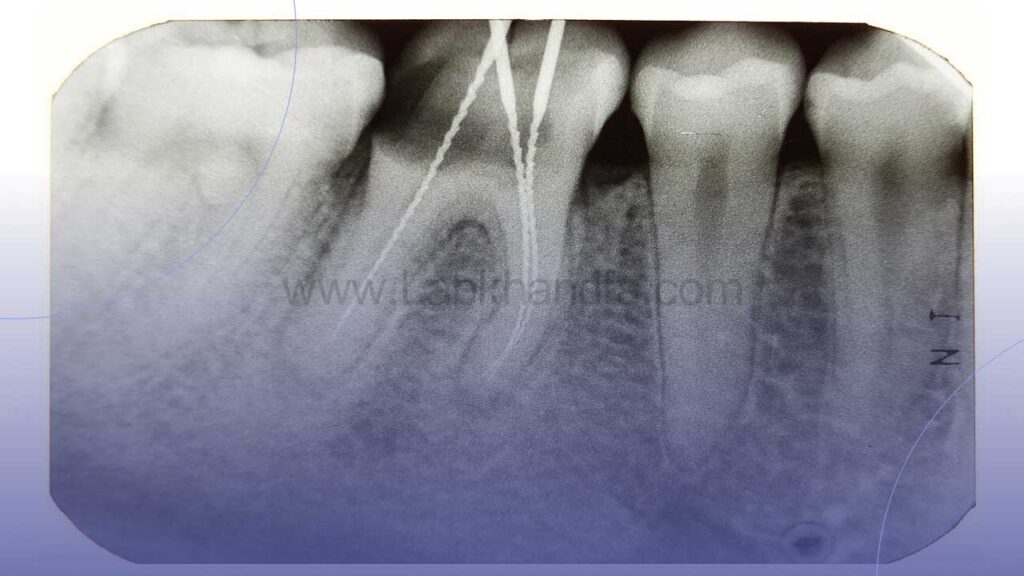

1. معاینه و عکس رادیوگرافی

ابتدا متخصص درمان ریشه با استفاده از عکس رادیوگرافی و در صورت نیاز سی تی اسکن دندانی، وضعیت ریشه ها، پرکردگی قبلی و وجود عفونت را ارزیابی می کند.